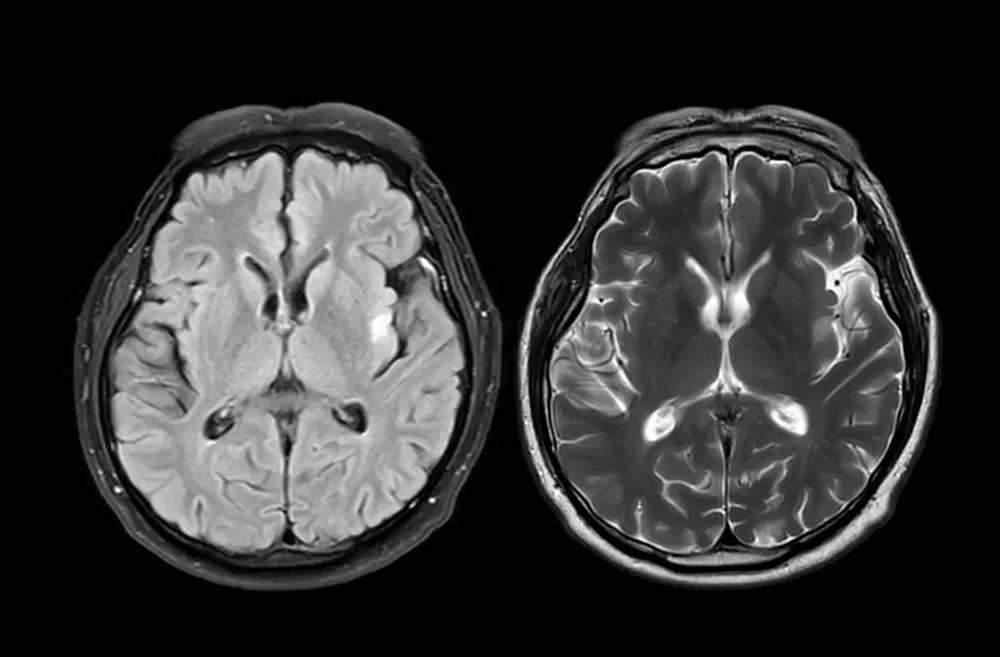

MRI brain scan axial T1W for detect Brain diseases sush as stroke disease, Brain tumors and Infections.